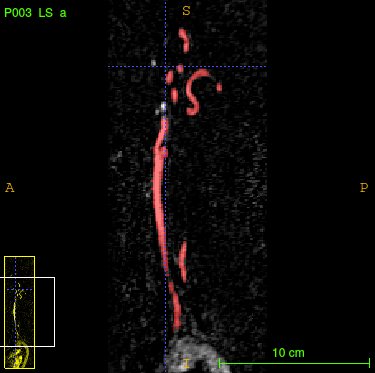

Refer to caption

Refer to caption\phantomcaption

Figure 5(): Ground truth (left), 3D segmentation mask generated by the 3D U-net (middle) and by the random 2.5D U-net (right).